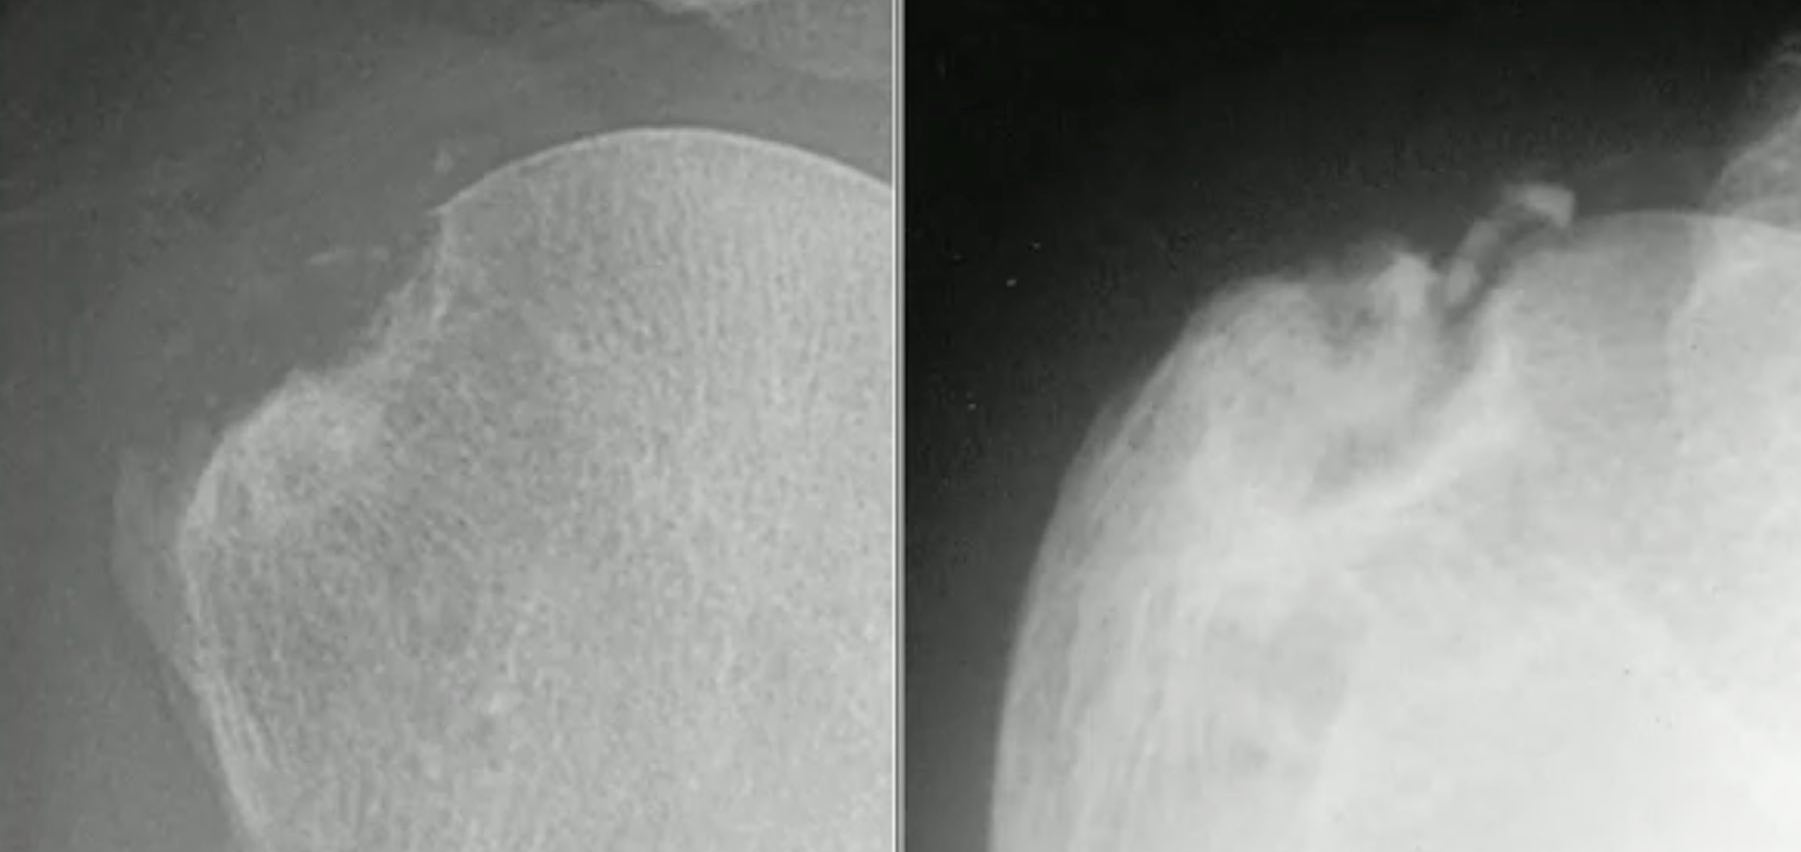

Goutte

1ère MTP > pied-cheville > membre sup.

- très grandes érosions bien limitées marginales/para-articulaires

- tophus périarticulaire ± proliférations osseuses réactionnelles

- pincement articulaire tardif et ∅ raréfaction os adjacent (≠ PR)